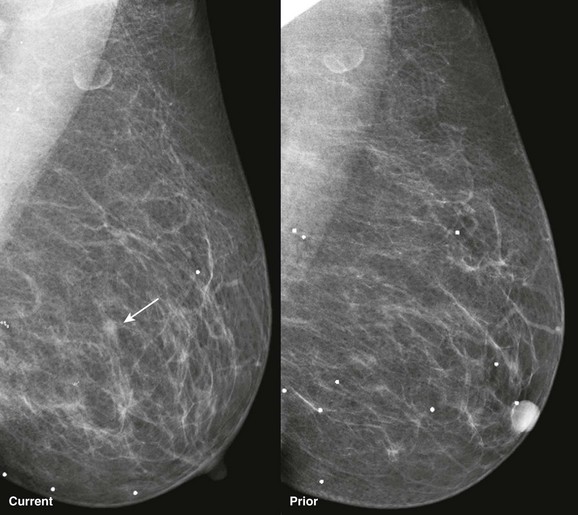

CASE 11-8. Mammography shows a large area of architectural distortion with skin retraction. US reveals extensive shadowing at the edge of the fibroglandular tissue. Diagnosis: ILC.

CASE 11-12. There is mild asymmetry in the area of the palpable region in the right breast. There is no distortion or discrete mass on mammography. On US, there are areas of shadowing with sonographic distortion. The presence of a clinically suspicious mass with asymmetry and sonographic shadowing suggests the diagnosis of ILC, which was the diagnosis. Congratulations if you were thinking ILC. Good job!